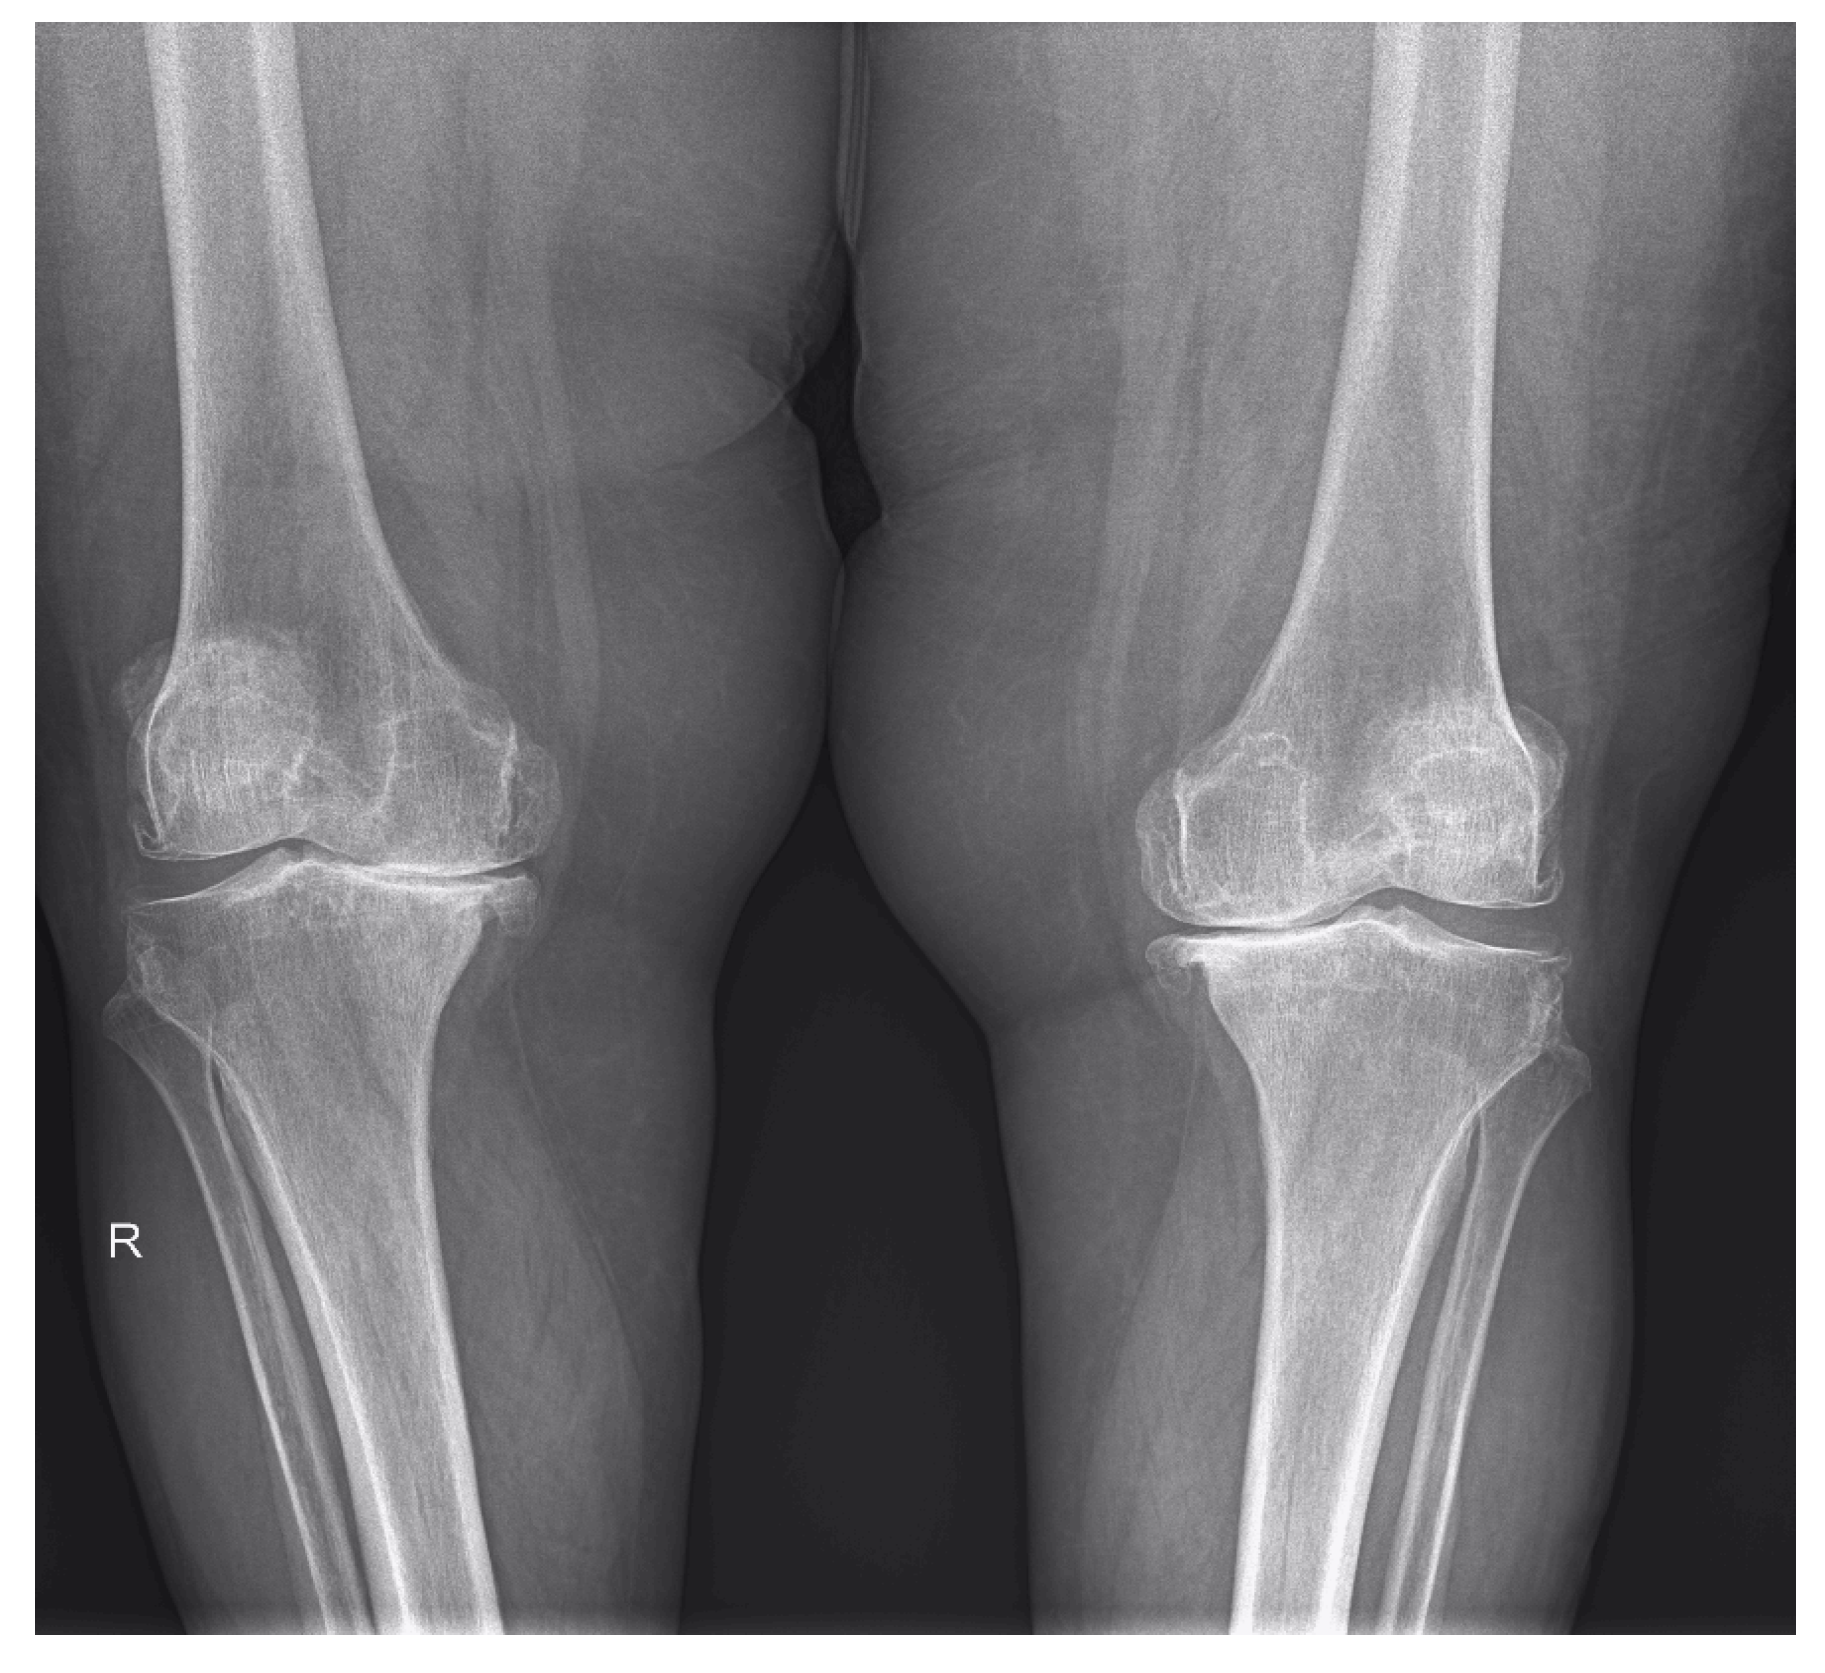

2.2. Demographic Characteristics and Assessment of Clinical, Laboratory and Imaging Data